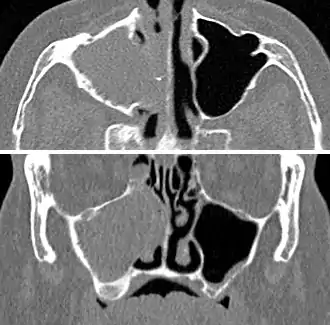

| A CT scan showing sinusitis of the ethmoid sinus | |

For sinusitis lasting more than 12 weeks, a CT scan is recommended.[53] On a CT scan, acute sinus secretions have a radiodensity of 10 to 25 Hounsfield units (HU), but in a more chronic state they become more viscous, with a radiodensity of 30 to 60 HU.[55]

CT of chronic sinusitis

CT scan of chronic sinusitis, showing a filled right maxillary sinus with sclerotic thickened bone.